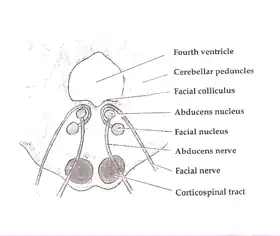

The facial colliculus is formed by brachial motor nerve fibres of the facial nerve (CN VII) looping over the (ipsilateral) abducens nucleus, forming a bump upon the surface.[1]

A facial colliculus lesion would result in ipsilateral facial paralysis (i.e. Bell's palsy) and inhibited ipsilateral and unopposed contralateral eye deviation.[2]

Axial section of the Brainstem (Pons) at the level of the Facial Colliculus